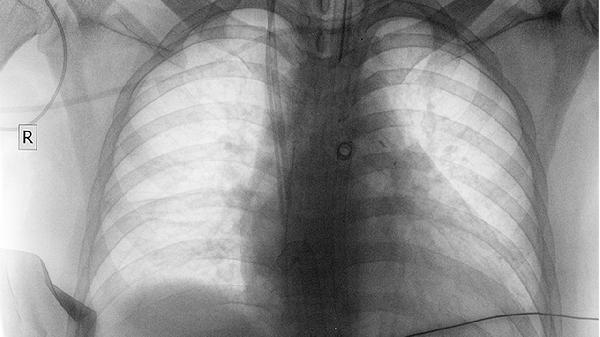

中晚期肺癌患者常出现进行性加重的呼吸困难,早期可能仅在活动后出现,后期静息时也会感到气促。呼吸困难可能与肿瘤阻塞气道、大量胸腔积液或肺不张有关。患者常需采取端坐呼吸体位缓解症状,严重时可出现口唇紫绀等缺氧表现。